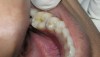

The search for an ideal direct esthetic restorative material is still ongoing. Among the array of RBC materials, some are readily available in the market (flowable, packable, and fiber-reinforced), others have just recently been introduced (siloranes-based), and a few are still in development phase (fluoride-releasing). Individual properties of different RBC materials define their advantages, disadvantages, and clinical uses. Each type of RBC material has its own virtues in some clinical aspects and shortcomings in other aspects. Every material possesses either one or the other ideal properties of a restorative material, but not all of them. Therefore, it is important for a clinician to use every material judiciously and for a clinical application for which it is best suited (Figure 5, Figure 6, Figure 7, Figure 8, Figure 9 and Figure 10).

Figure 7  defective amalgam restoration with fractured cusp restored with packable RBC

Figure 7